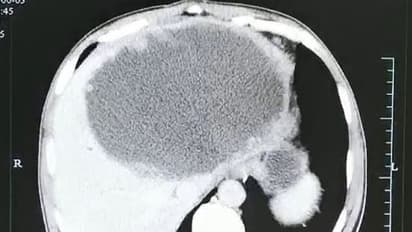

കടുത്ത വയറുവേദന മൂലം ആശുപത്രിയിലെത്തിയ അമ്പത്തിയഞ്ചുകാരന്റെ എക്സ് റേ ഫലം കണ്ട ഡോക്ടര്മാര് പോലും ഞെട്ടിത്തരിച്ചുപോയി. കരളിന്റെ വലത്തേ ഭാഗത്ത് മുഴുവനായി പഴുപ്പ് നിറഞ്ഞത് പോലെ തീരെ ചെറിയ മുഴകള് കൊണ്ട് നിറഞ്ഞിരിക്കുന്നു. ഇത് എന്ത് പറ്റിയതാണെന്ന് മാത്രം ആദ്യം ഡോക്ടര്മാര്ക്ക് മനസിലായില്ല.

ഇതിന്റെ മാംസത്തില് നിന്നും ചെറിയ വിരകള് (പാരസൈറ്റ്) അദ്ദേഹത്തിന്റെ ശരീരത്തില് കയറിപ്പറ്റി. ശേഷം കരളിന്റെ വലത്തേ അറയിലായി വിരകള് താമസവും തുടങ്ങി. മാസങ്ങള് കൊണ്ട് ഇവ അവിടെ മുട്ടയിട്ട് പെറ്റ് പെരുകി. പഴുപ്പ് നിറഞ്ഞത് പോലെ എക്സ് റേയില് കണ്ട തീരെ സൂക്ഷ്മമായ മുഴകളെല്ലാം തന്നെ ഈ മുട്ടകളായിരുന്നത്രേ.

സംഗതി വ്യക്തമായതിനെ തുടര്ന്ന് ഡോക്ടര്മാര് ആദ്യം കരളില് നിന്ന് നീര് കുത്തിയെടുത്ത് ചികിത്സ തുടങ്ങി. എന്നാല് അതുകൊണ്ട് മാത്രം അദ്ദേഹം രക്ഷപ്പെടില്ലെന്ന് മനസിലാക്കിയതിനെ തുടര്ന്ന് ശസ്ത്രക്രിയയിലൂടെ കരളിന്റെ ഒരു ഭാഗം തന്നെ മുറിച്ചുമാറ്റി.